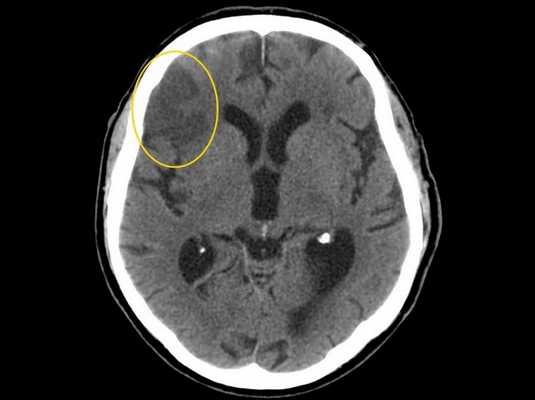

Облучение при КТ головного мозга

Компьютерная томография визуализирует состояние костей черепа, показывает изменение строения церебральных структур. Метод используют при травмах головы, воспалительных процессах, ишемических и геморрагических инсультах.

Нативное исследование внутричерепного пространства занимает 5-15 минут. Доза облучения, которую получает пациент при КТ головного мозга, составляет 1-2 мЗв. Уровень радиоактивного воздействия зависит от напряжения и силы тока в рентгеновской трубке, количества сканируемых срезов за полный круг гентри, ширины шага и пр. Нагрузка при компьютерной томографии головы соответствует естественной дозе радиации, получаемой человеком за 2-5 лет.

Во время КТ пациенту следует соблюдать неподвижность и выполнять рекомендации врача. При изменении положения тела возможно появление дефектов на томограммах. Искажение картины сканирования приводит к необходимости проведения повторных сканирований.

Ишемический инсульт головного мозга (зона поражения выделена желтым) на снимке КТ

С учетом прописанных в СанПиНе норм в год пациент может проходить не более 2 обследований.